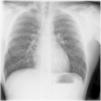

The authors present the case of a 21-year-old male professional fisherman, who, after 90 min of surface diving, increased dive depth to seven meters with compressed air bottle. At this point he emerged rapidly after feeling an unusual thoracic discomfort, which become worse as he ascended. Immediately after the emersion he developed complaints of cervical swelling and dysphonia, and was admitted to our hospital emergency department. Physical examination revealed a subcutaneous cervical and supraclavicular emphysema in chest radiography (Fig. 1), which later extended to the abdominal region. The patient remained hemodynamically stable, with peripheral oximetry between 98 and 100% breathing room air.